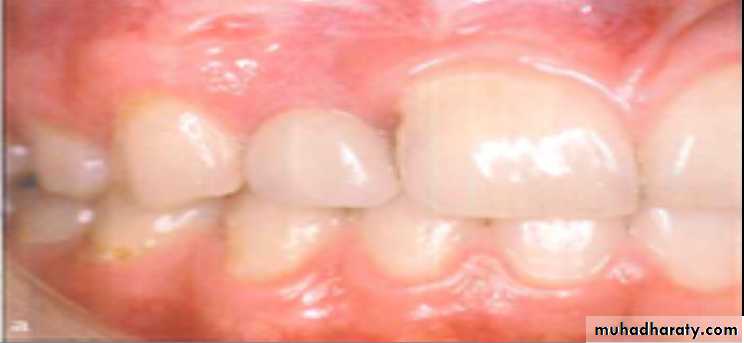

Adverse Effect of Labial/ Buccal Tooth Movements

Labial and buccal tooth movement displace the root toward, and sometimes through the cortical plate. If more toque is incorporated into the archwire, the magnitude of force is increased and the apex may be displaced through the cortical bone, resulting in a fenestrationContrary to the bone fenestration, which is localized in the apical part of the root , A bone dehiscence involves marginal bone loss at the labial / buccal aspects of the root

Marginal bone recession displacement of the soft tissue margin apical to CEJ with exposure of the root surface, is a common feature in individuals who have not undergo orthodontic treatment. Such recessions are also observed in association with orthodontic therapy, for example , after alignment of crowded teeth .This type of recession may be associated with localized plaque- induced inflammatory lesions.

As long as the tooth can be moved within the envelop of the alveolar process, risk of development of harmful side effects in the marginal tissue is minimal regardless of the dimension and quality of the soft tissue. If the tooth movement result in an alveolar bone dehiscence, it must be stressed that no bone regeneration occur, even after a long period of retention. The volume (thickness) of the soft tissue cover should be considered as a factor that may cause a soft tissue recession to develop during or after active orthodontic treatment.